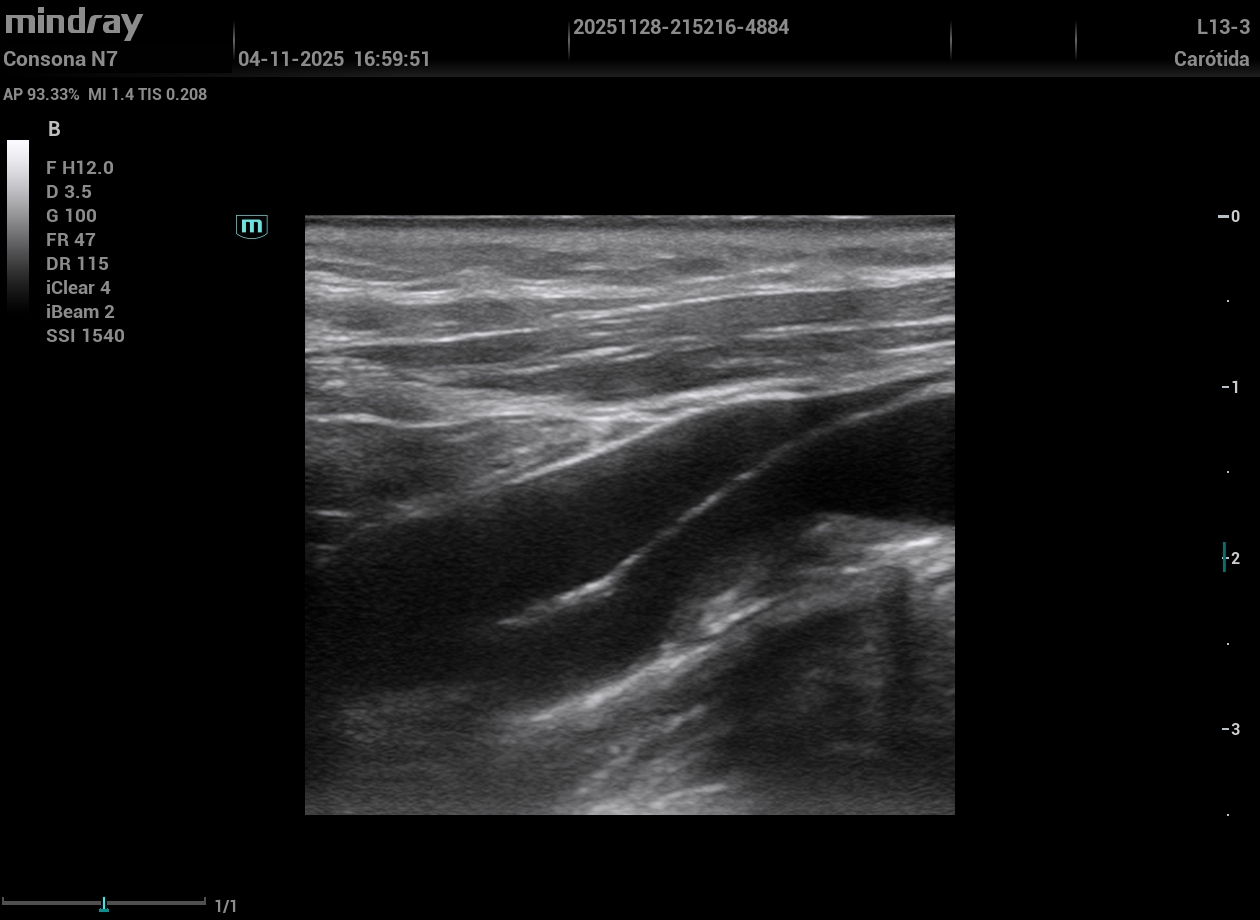

Eco vascular protocolo VASUS +: grandes placas de ateroma tipo 2-3 en ambas carótidas visualizando en carótida interna derecha una obstrucción de más del 50%; ambas femorales con alta carga de placas. ETT: FEVI conservada. HVI concéntrica.